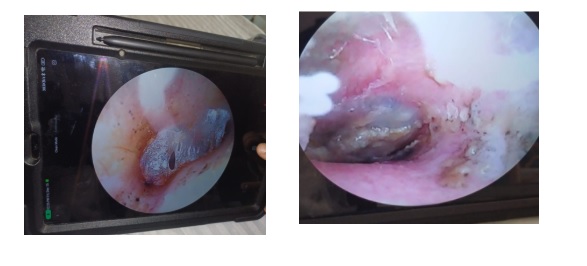

IMAGE 1– A thin, transparent, network-like appearance marked the initial approach to the case.

IMAGE 2 -The discharge manifested a wet, paper-like appearance with a distinct yellowish-green color.